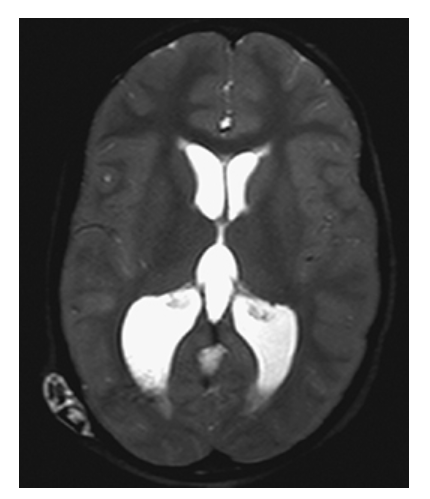

Hydrocephalus. T2W axial image shows high-signal CSF within markedly dilated lateral ventricles as a result of a shunt malfunction (fluid leaking around shunt in right parieto-occipital soft tissues).